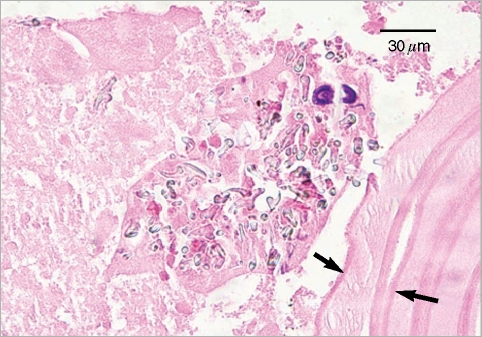

An Imported Case of Echinococcosis of the Liver in a Korean Who Traveled to Western and Central Europe

The Korean Journal of Parasitology 2010;48(2):161-165.